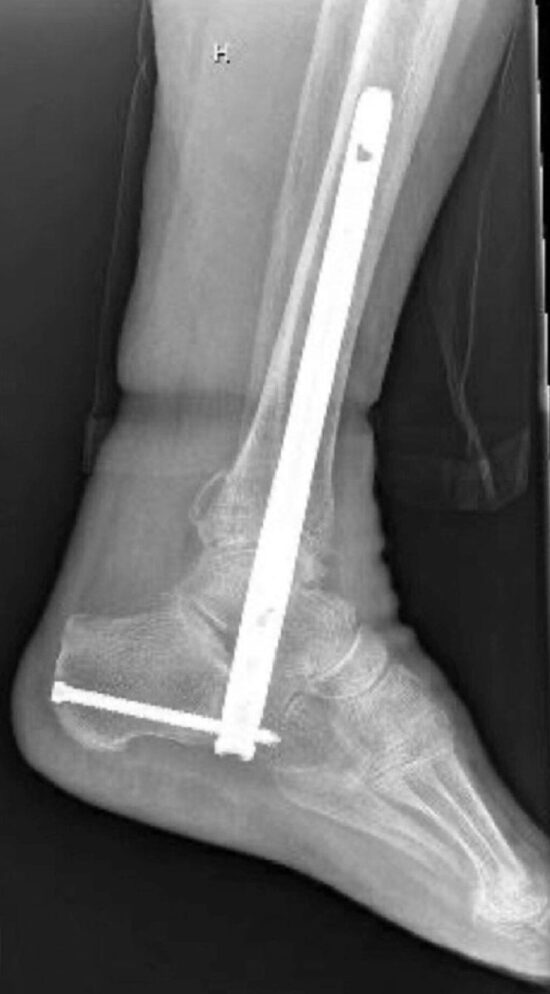

There were 22 patients (average age 80.8 years). Mean LOS was 7.0 days, and 68.2% were discharged to subacute rehabilitation. Within 30 days, 1 patient developed a deep vein thrombosis and bilateral pulmonary emboli, and 2 experienced wound dehiscence requiring antibiotics. At 6 weeks, 1 patient sustained a fall with periprosthetic fracture requiring HFN revision, and another developed cellulitis necessitating hardware removal. Fracture healing was seen in 72.7% at 19.4 weeks, while radiographic fusion occurred in 18.2% at 43.0 weeks. 72.7% were ambulating with an assistive device at discharge, and 100.0% at 12-weeks post-operatively or last follow-up. All patients were ambulating without pain, upon final examination.

As a reliable alternative to traditional open reduction internal fixation, HFNs have the ability to improve quality of life for geriatric patients through a faster return to weight bearing. Additionally, radiographic fusion rates show that patients have favorable functional outcomes even without formal arthrodesis.

The authors concluded that HFN is beneficial for elderly patients with low functional demand and complex medical comorbidities, as it allows for early mobility after sustaining an ankle or distal tibia fracture.